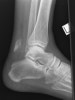

X-ray : Lover’s fracture

X-ray : Calcaneal tuberosity avulsion fracture